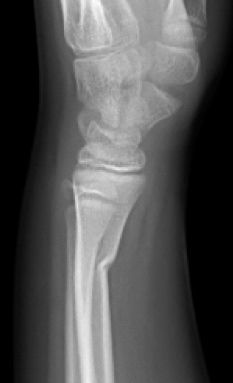

C. Fracturas en tallo verde

Las fracturas de tallo verde, cuando permanece una parte del periostio intacta y la otra cortical está desplazada, son diferentes de las fracturas en rodete, en las que existe un típico “abombamiento” del hueso metafisario (Figura 13).

Figura 13: a, b, Radiografía antero-posterior y lateral donde se aprecia un “abombamiento” de la región metafisaria distal del radio compatible con fractura en rodete.